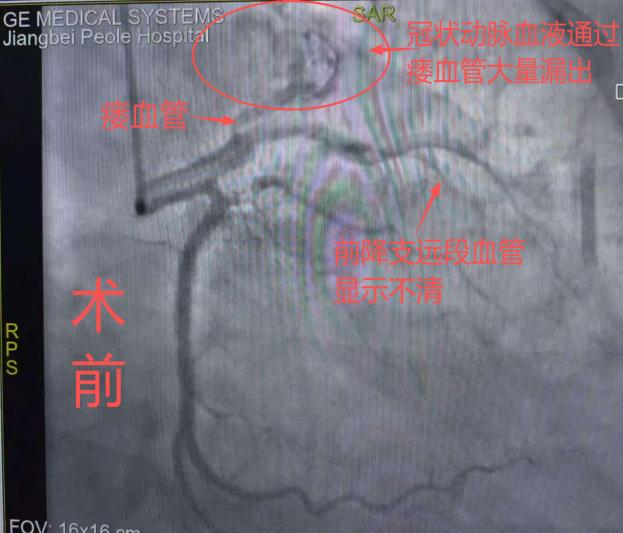

【临床动态】不用开胸!我院首例冠状动脉瘘介入封堵术成功实施,患者术后恢复..